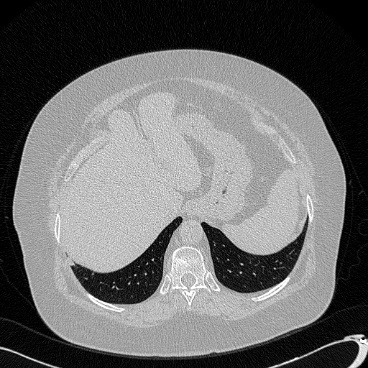

相关图片展示: